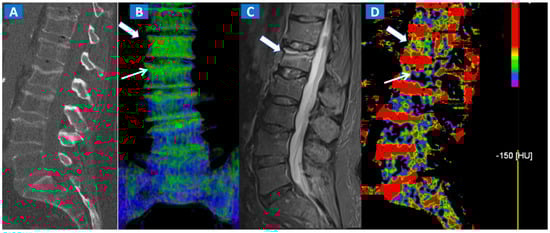

Figure 1.

A 43-year-old male with low back pain following high-energy trauma, with no vertebral fractures. On the sagittal STIR MRI image (A), all lumbar vertebral bodies show a normal shape and signal intensity. On the 3D DECT image, on the para-sagittal plane (B), normal vertebral bodies are coded in blue, whereas density increases, due to increased water content, are coded in green. As expected, the normal intervertebral discs are coded in green. In addition, normal cortical bone is also coded in green, due to an incomplete subtraction process. On the corresponding 1 mm sagittal 2D DECT image (C) there is a color lookup table that codes bone marrow and areas of oedema in shades of green-yellow to orange-red. DE-specific information has been fused with conventional grayscale morphological images (thickness, 1 mm; increment, 1 mm). The range of densities is set between −150 and 100 HU, with underlying normal bone visualized without any superimposition for density values below the −50 HU cut-off.

Figure 2.

A 62-year-old female with traumatic low back pain following a fall. On the sagittal standard 1 mm CT image (A) it is not possible to identify the fresh fracture. On the coronal 3D DECT image (B), BME of the L1 vertebral body is coded in green (thick arrow), with some mild oedema depicted on the L2 superior endplate (thin arrow). On the sagittal STIR MRI image (C), a fresh fracture of the L1 body is confirmed, with mild oedema located close to the superior endplate (thick arrow). There is no BME of the L2 body apparent on the STIR MRI image. On the corresponding 2D DECT image (D), the maximum level of superimposition of color-coded maps was used to confirm the presence of mild oedema on the L1 vertebral body (thick arrow) and to rule out the presence of significant oedema on the L2 body (thin arrow), thus avoiding a false positive finding.